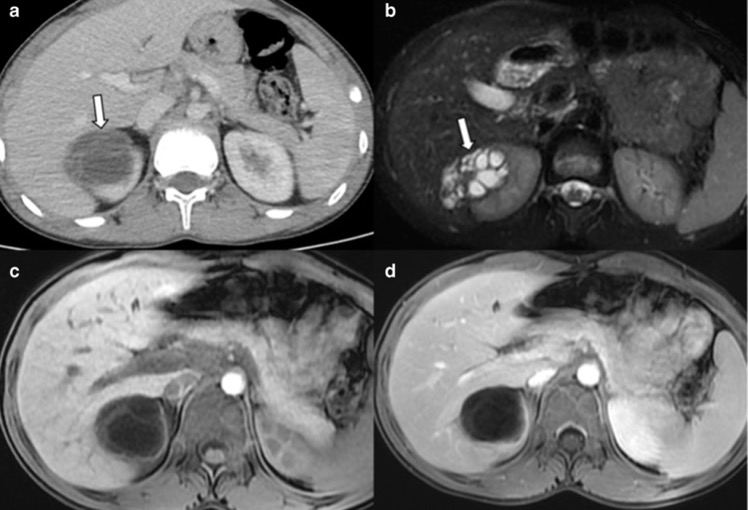

- Kyste rénal hémorragique